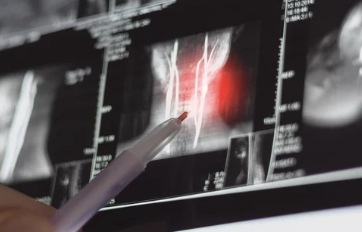

6. 수술적 치료 방법

수술이 필요한 경우

- 약물 및 물리치료에도 증상이 호전되지 않는 경우.

- 신경이 심각하게 눌려 근육 약화나 마비가 발생한 경우.

주요 수술법

- 미세 디스크 제거술: 탈출된 디스크를 제거해 신경 압박 해소.

- 인공 디스크 삽입술: 손상된 디스크를 인공 디스크로 교체.

- 레이저 치료: 디스크를 줄이는 비침습적 방법.

수술은 마지막 단계로 고려되며, 전문의와 충분한 상담이 필요합니다.